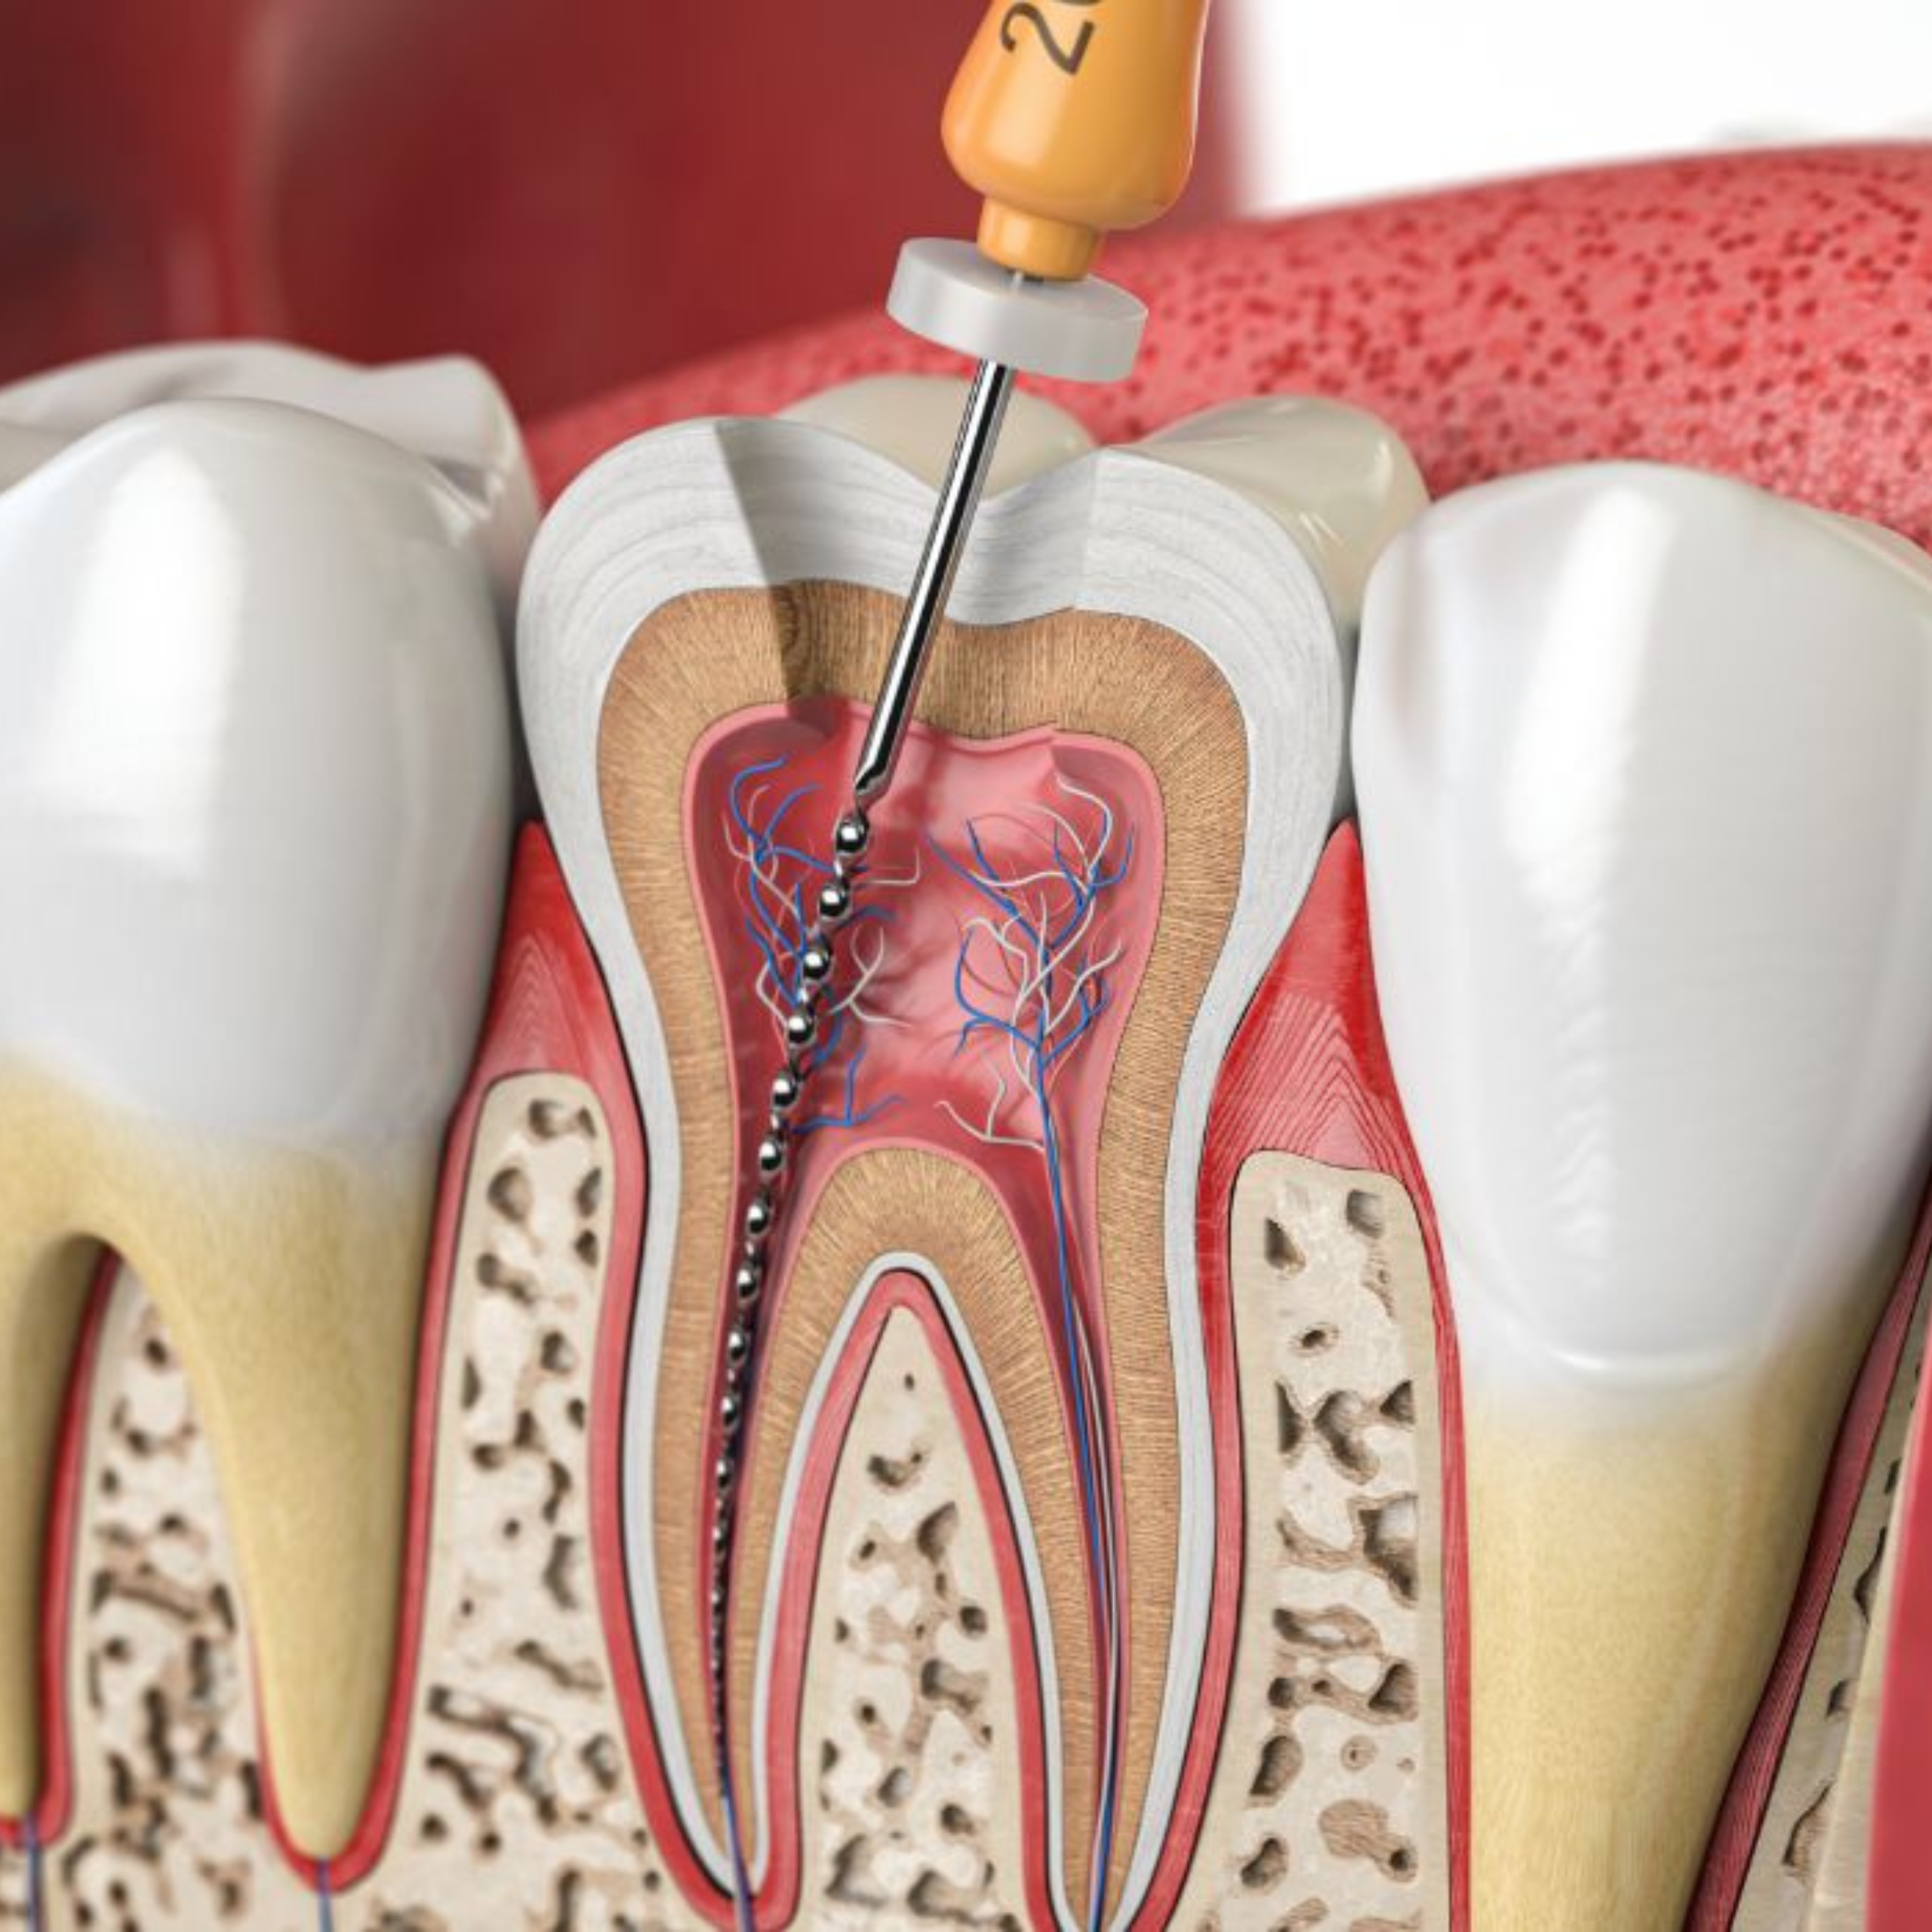

Lorsqu’une carie atteint la pulpe dentaire, un traitement endodontique (traitement de canal) est nécessaire.

Grâce à une technologie de microscopie et des instruments modernes, le Dr. Soumaya BenHamza nettoie et scelle le canal avec une précision exceptionnelle, permettant à votre dent de rester en place et de fonctionner normalement.